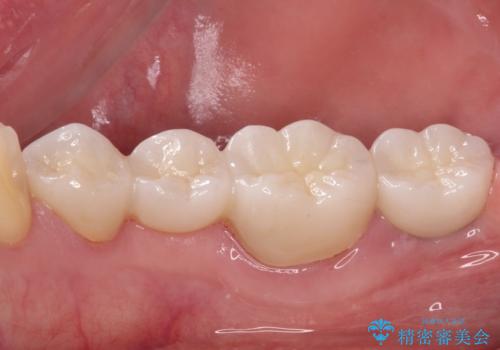

抜歯してからインプラント埋入までには時間がかかるため、その間に下顎左右臼歯の金属のブリッジをオールセラミックへ変えていくこととしました。

目立つ部分の銀歯や気になる変色歯をまとめてきれいに仕上げることができました。